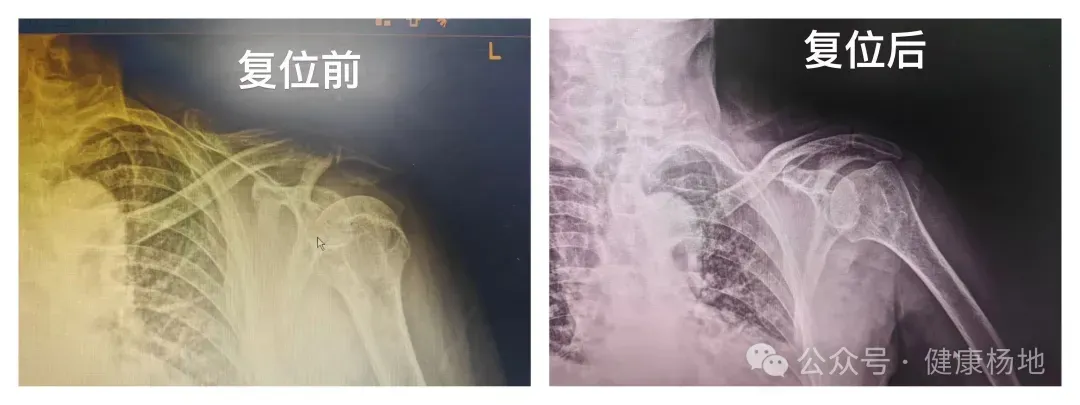

患者因摔倒导致左肩关节疼痛、活动受限3天来院就诊,接诊医生王伟第一时间为其完善肩关节正位片检查,提示左肩关节间隙增宽,明确诊断为左肩关节脱位。考虑到患者年事已高,身体耐受度较低,且家属希望减少医疗开销、规避药物副作用,王伟医生结合老年患者诊疗特点,精准评估排除复位禁忌后,制定了Kocher旋转法纯手法复位方案,全程不使用任何药物、不输液,最大程度降低诊疗对老人身体的负担。

复位过程中,王伟医生凭借丰富的临床经验和娴熟的操作技巧,严格遵循老年骨科微创诊疗原则,精准把控发力角度与力度,动作沉稳规范。复位后即刻复查X线,显示患者左肩关节位置、结构恢复正常,原本的疼痛与活动受限问题得到快速缓解。随后为患者予悬吊带屈肘90°贴胸固定,详细告知家属固定注意事项及后续康复要点,患者顺利离院,家属对诊疗效果连连称赞。